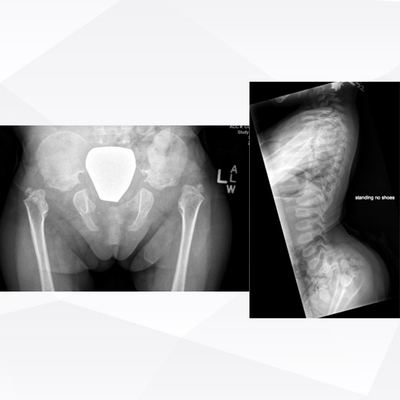

Click on an image below to view more info.